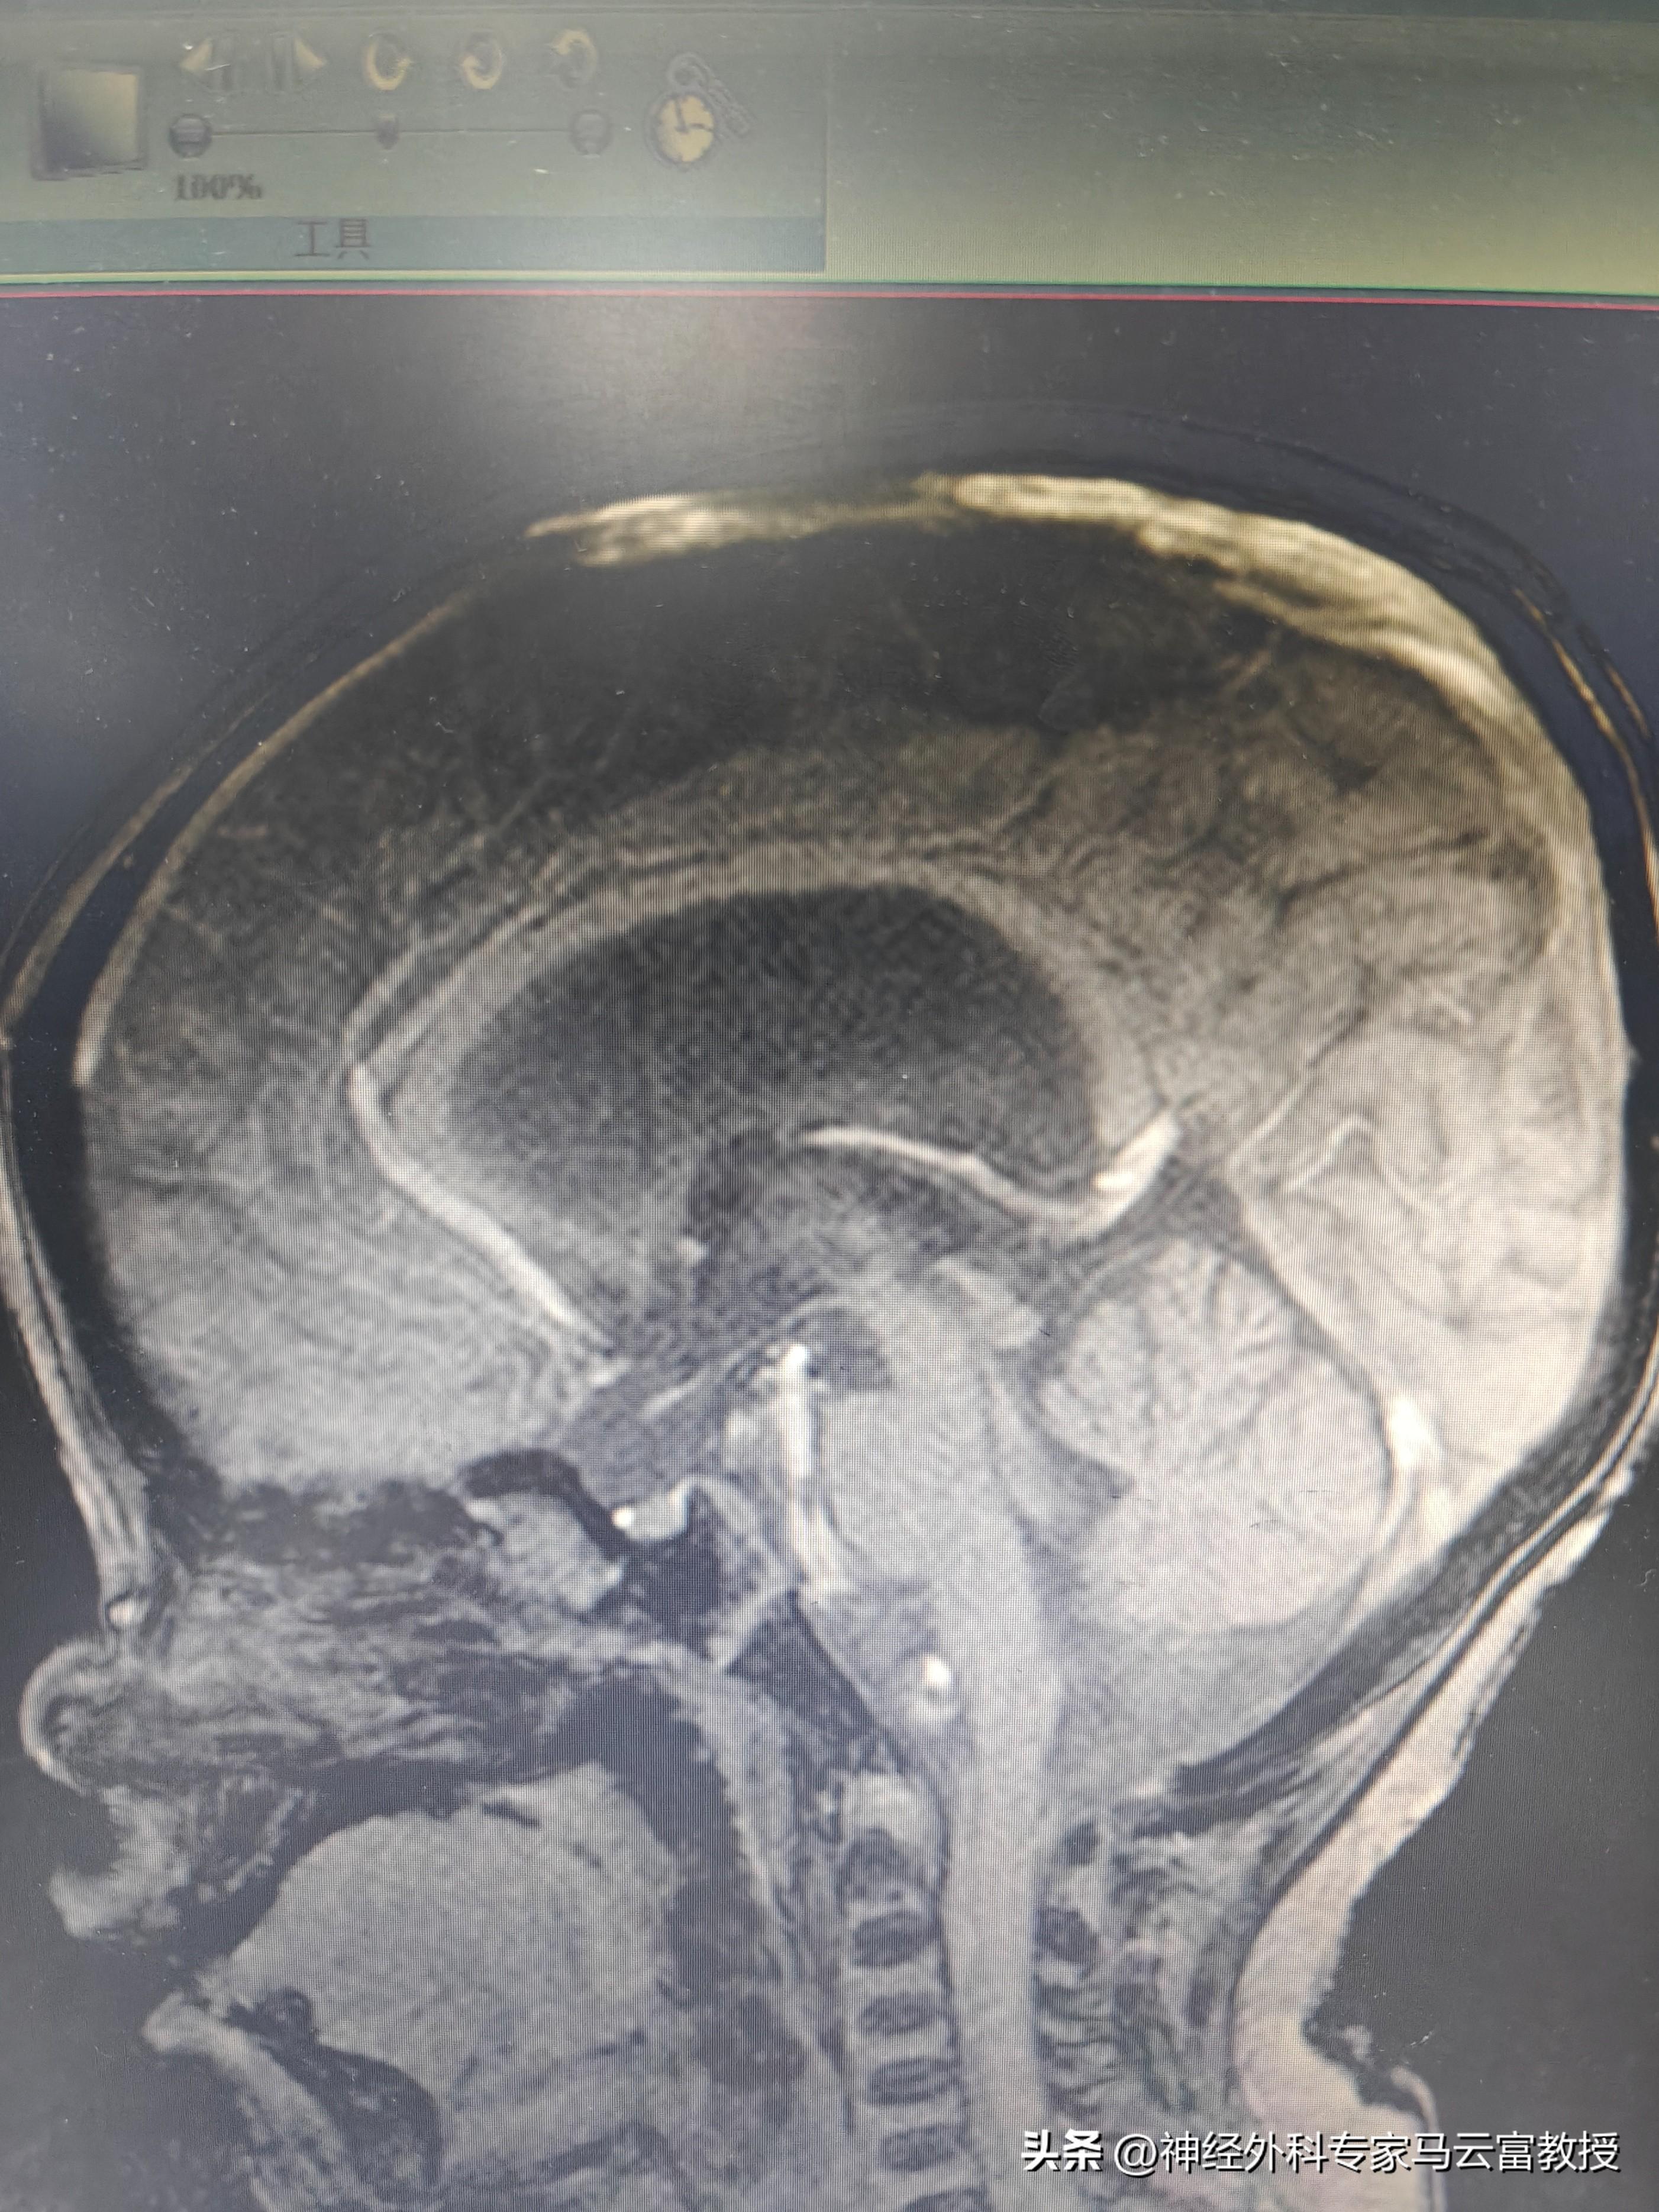

孩子頭圍已達57cm(遠超同齡正常水平),發育也明顯滯後,目前僅能發出 “爸爸”“媽媽” 的簡單音節。在當地醫院檢查時,醫生髮現寶寶側腦室正在逐漸增寬,建議立即轉診至我院進一步診治。

我院神經外科馬雲富主任接診後,通過細緻查體與顱腦 CT 檢查,明確診斷爲幕上腦積水。入院後,團隊完善了腦 MRI + 腦脊液電影成像等精準檢查,最終判斷爲不全梗阻性腦積水,且腰穿提示腦室內壓力不高。綜合評估後,馬雲富主任爲患兒制定了腦室 - 腹腔分流術的治療方案,爲寶寶的大腦 “減壓”,重啓正常發育的可能。